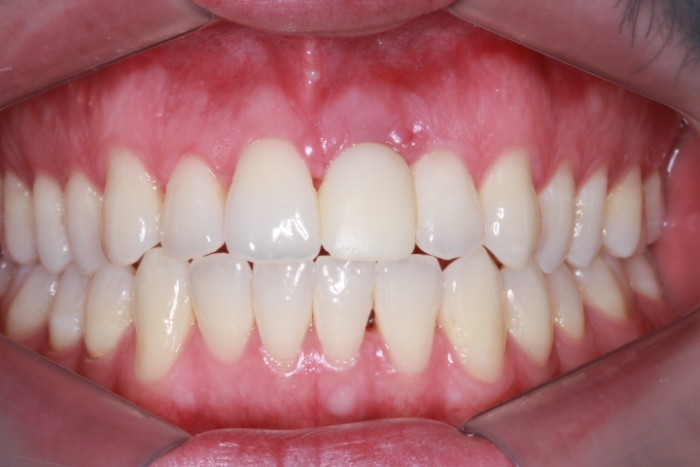

Imagem Final - Prótese Definitiva em Porcelana, em Novembro de 2015